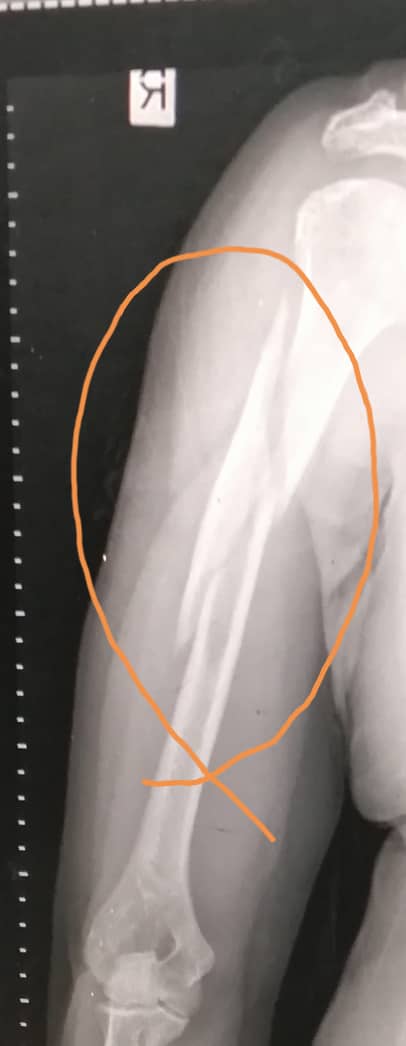

hospitalized simultaneously due to being infected with bone pain and